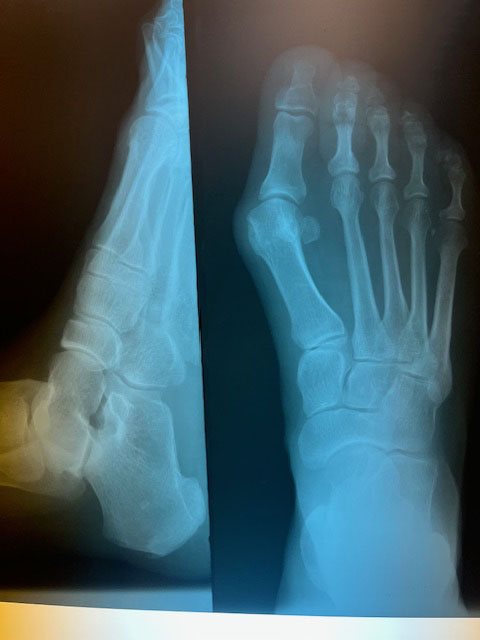

"Surgical misadventure" by another surgeon about 8 years ago. The wrong fixation was used for a flatfoot repair, & the deformity was not corrected. Patient came in with severe foot & ankle pain, with no arch at all. She was unable to play with her grandchild because the pain was so bad, & because she felt unsteady. The old hardware was removed, a lateral calcaneal lengthening osteotomy was performed along with a medial column/1st ray realignment. The ankle was painfully arthritic, & patient elected a total ankle replacement vs. an ankle fusion. She is now able to walk pain free & play with her grandchildren!